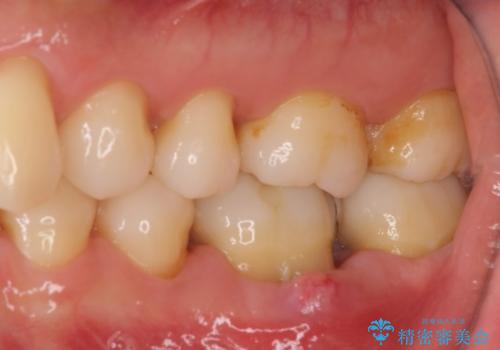

銀歯を外すと神経組織の一部が取り除かれており、歯根に付け根に穴が空けられている状態でした。

出血の原因は以前の治療で空けられた穴であると考え、封鎖をするとともに根管治療を行い、その後オールセラミッククラウンにて補綴治療を行うこととしました。